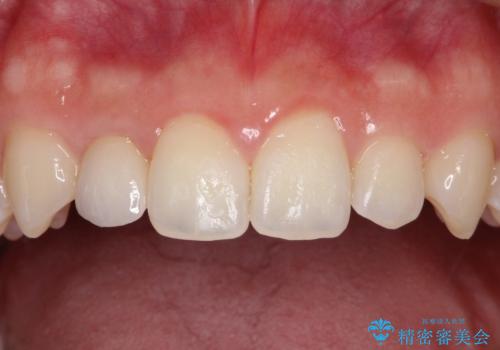

正中の隙間をインビザライン矯正で閉鎖して、右上の2番目の歯にはセラミックを装着する計画としました。

矯正治療とセラミック治療を組み合わせることにより、審美的により良い結果を得ることができました。